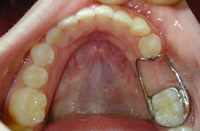

Space Maintenance

A baby tooth is sometimes lost prematurely because of tooth decay or injury. If this occurs before the permanent tooth is ready to erupt the nearby teeth can shift or drift into the space where the primary tooth use to be creating a lack of space in the jaw for the permanent teeth. The teeth in the other jaw may also move up or down to fill in the gap. If this crowding happens there may not be enough room for the new tooth to come in correctly, so it emerges lopsided or is not able to erupt at all. This crowded condition can make it more difficult :

Surprisingly some baby teeth are not replaced by adult teeth until a child reaches 12 or 14 years old!The space maintainer is a small metal device that is custom fitted to your child’s mouth. It is firmly fixed in the mouth and will be removed when the permanent tooth is in it’s proper position. It may consist of a band attached to the tooth on one side of the space with a wire loop or spring bridging the gap to the tooth on the other side. They steady the remaining teeth, preventing movement until the permanent tooth takes it’s natural position.